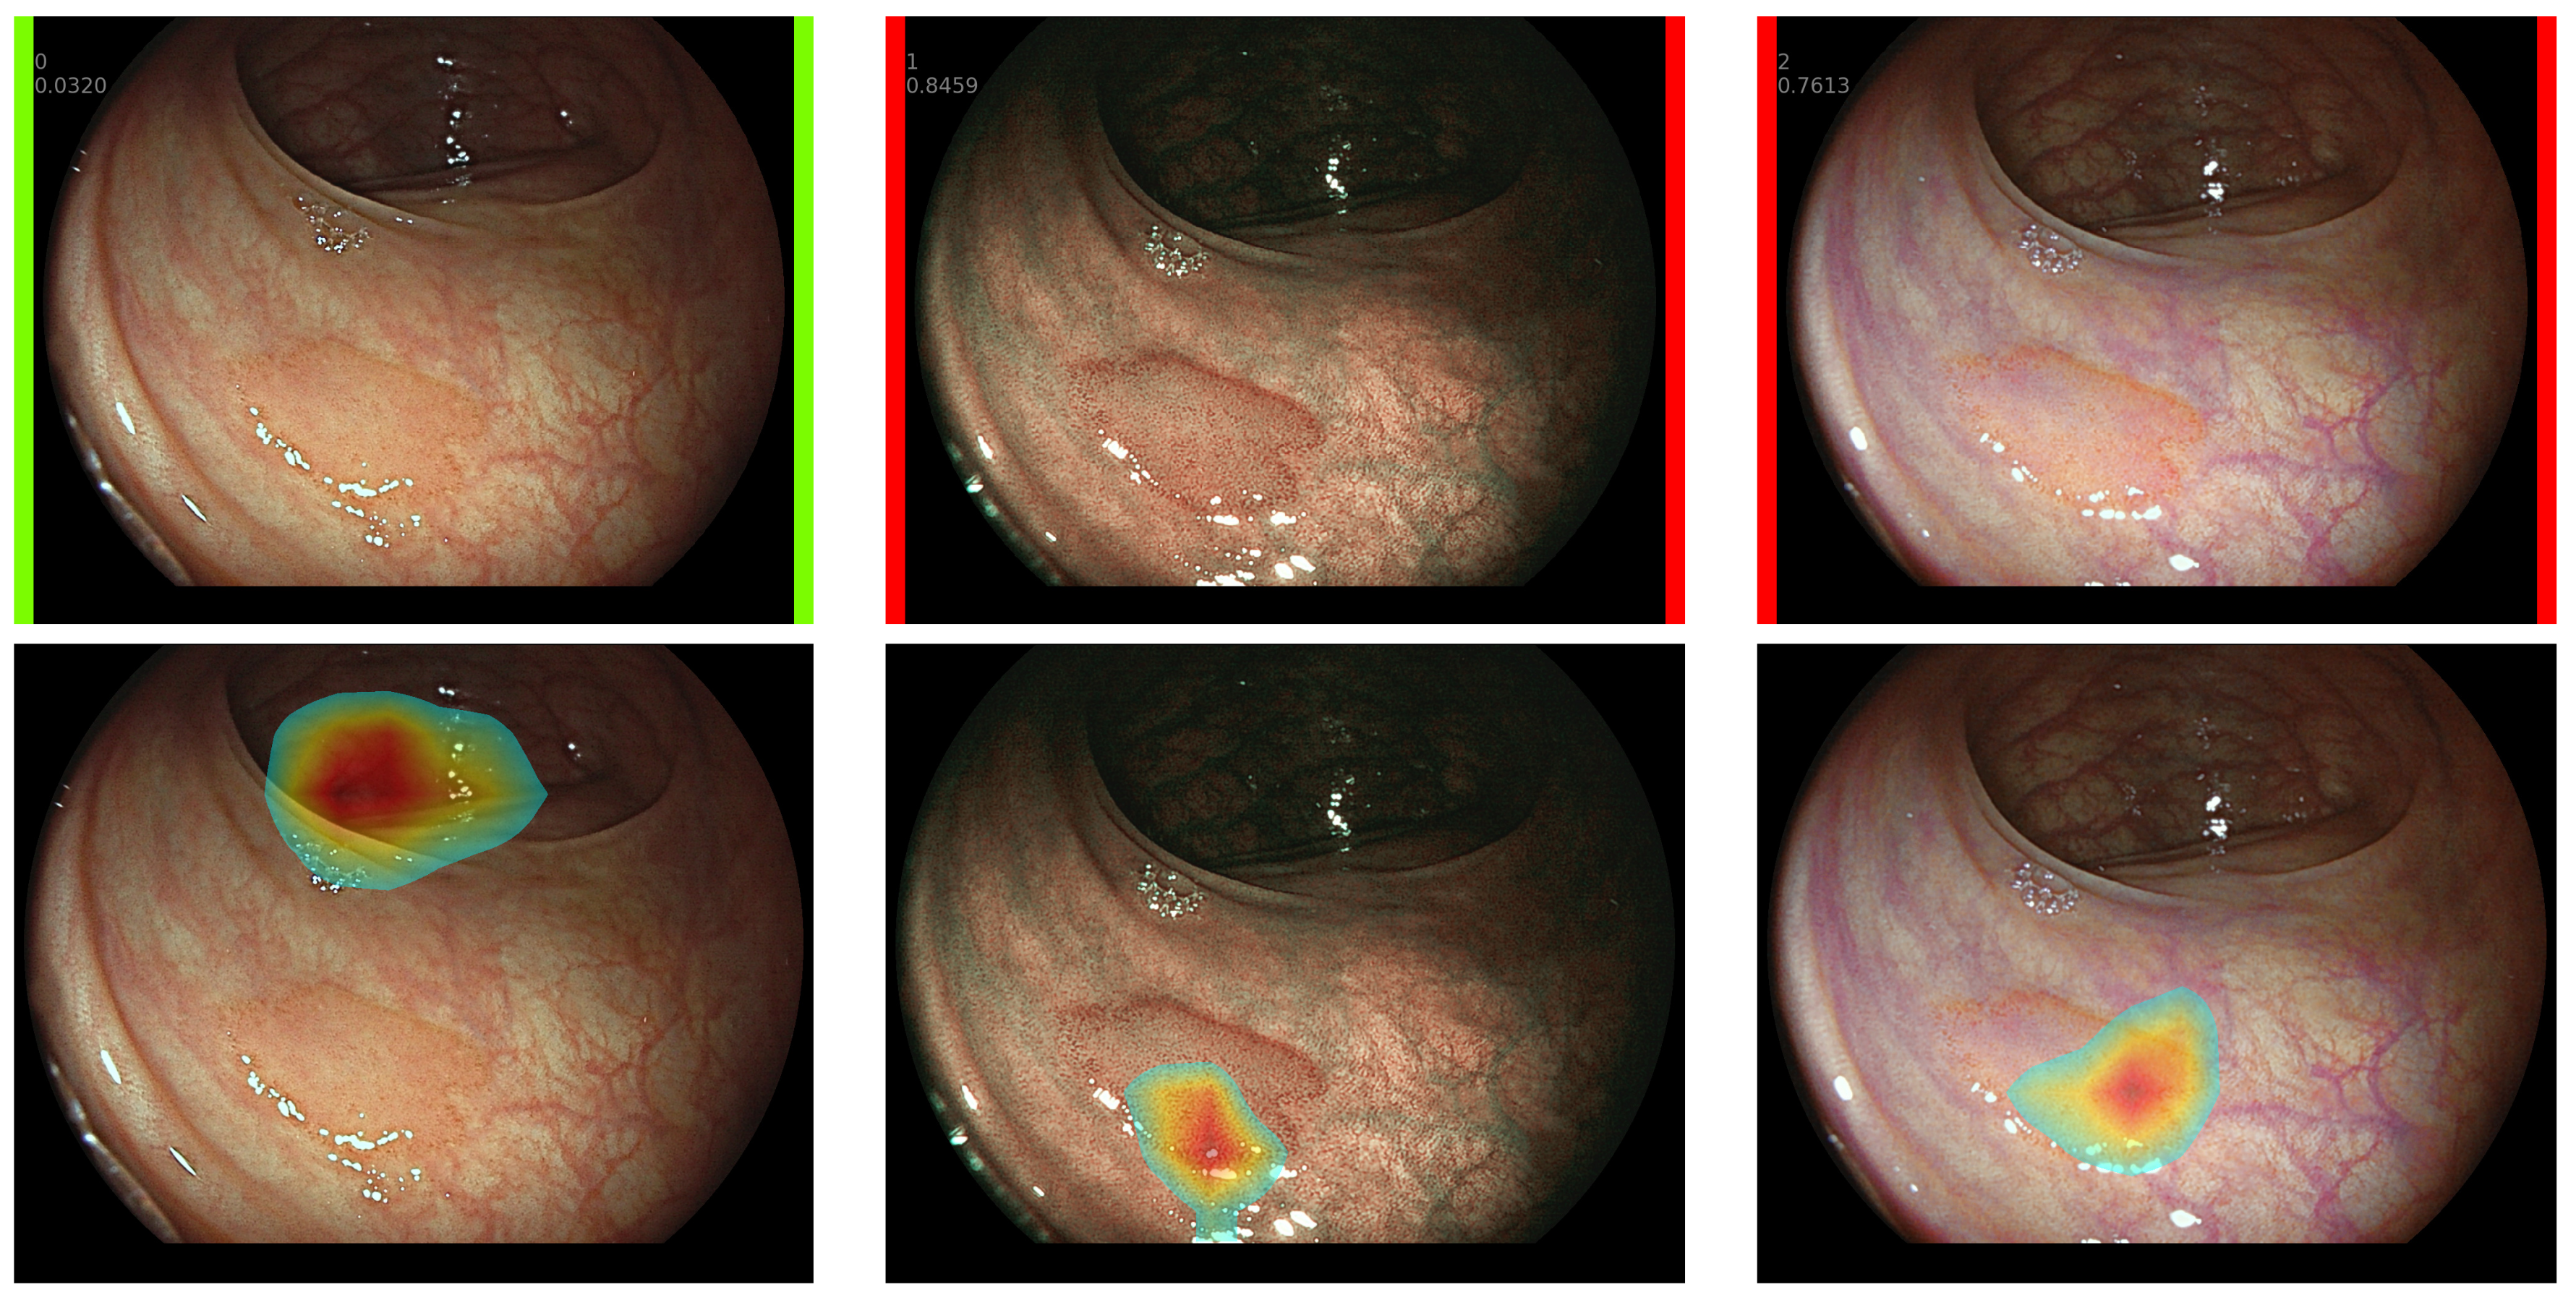

- Our developed CADx systems provides explainable visual data from the CNN to contribute to smooth decision-making.

2.5. Explainable CADx System

- Selvaraju, R.R.; Cogswell, M.; Das, A.; Vedantam, R.; Parikh, D.; Batra, D. Grad-CAM: Visual Explanations from Deep Networks via Gradient-Based Localization. Int. Comput. Vis. 2019, 128, 336–359. [Google Scholar] [CrossRef]